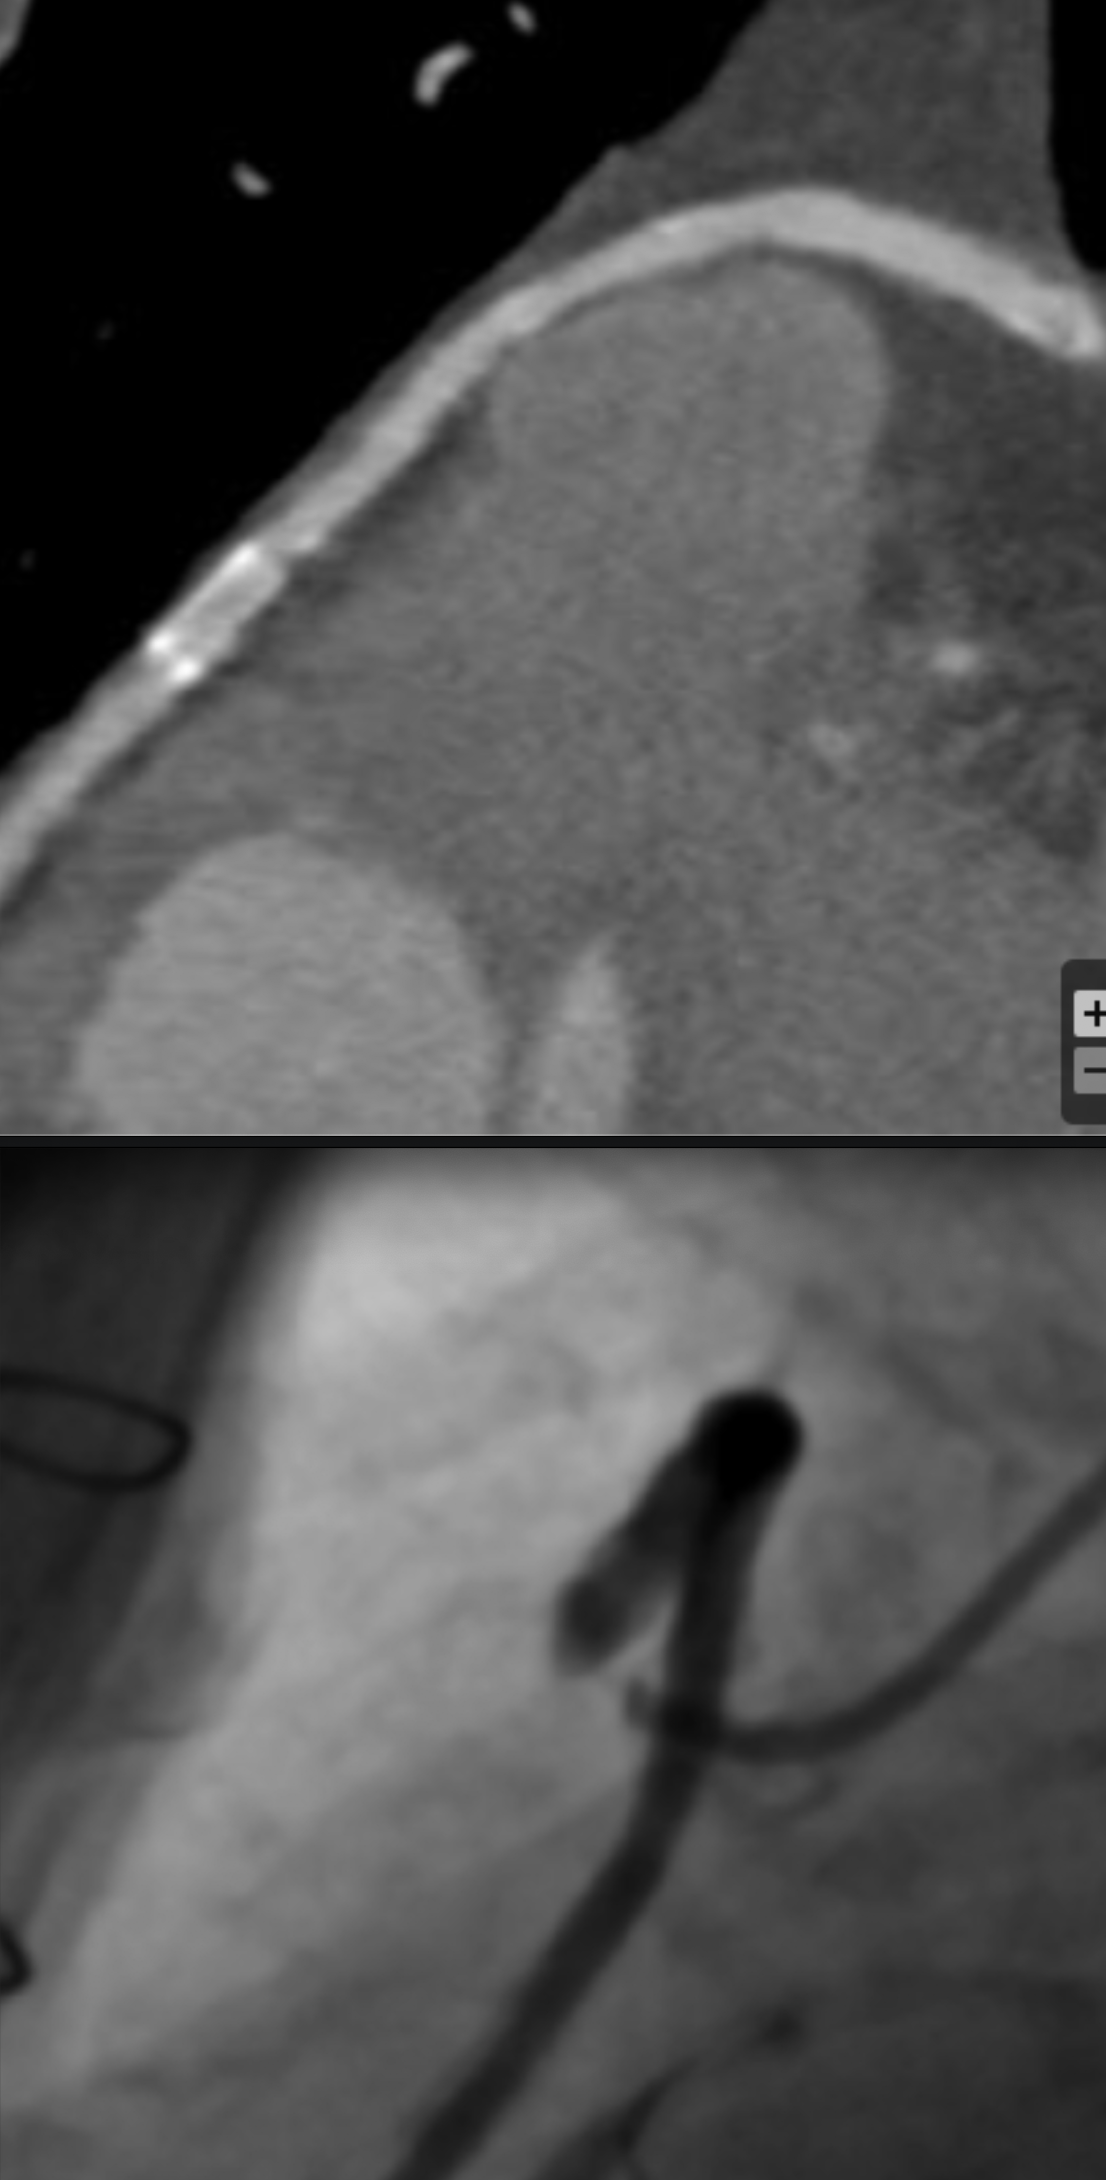

Describe the findings:

Beam Hardening Artifact